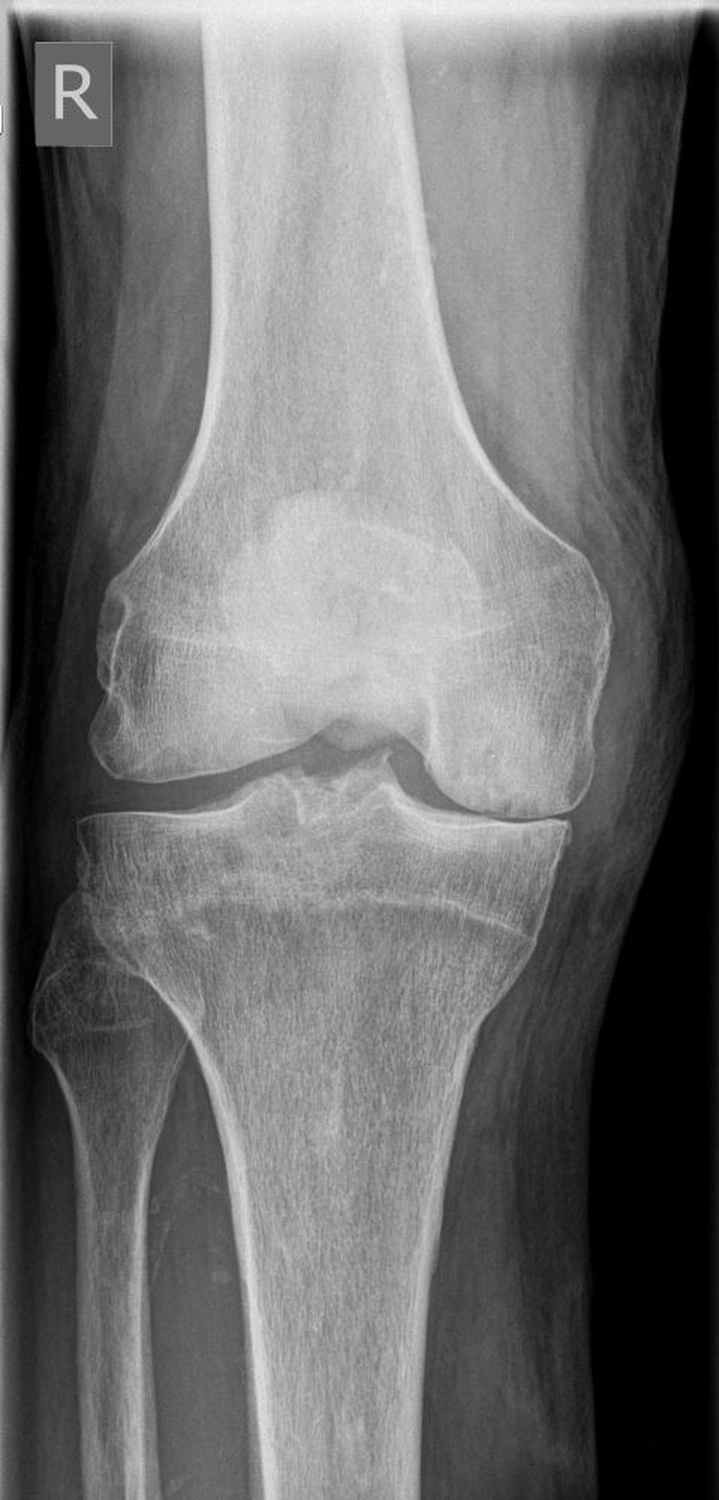

Das Kniegelenk ist das größte und eines der am stärksten belasteten Gelenke des menschlichen Körpers. Bei jeder Bewegung – Gehen, Treppensteigen, Hocken oder Stehen – wirken erhebliche Kräfte auf die Gelenkflächen von Oberschenkelknochen (Femur), Schienbein (Tibia) und Kniescheibe (Patella).

Diese Flächen sind von einer glatten Knorpelschicht überzogen, die wie ein Stoßdämpfer wirkt und ein reibungsloses Gleiten ermöglicht. Im Verlauf des Lebens kann sich dieser Knorpel jedoch abnutzen oder geschädigt werden – man spricht dann von einer Arthrose.

Die Kniegelenksarthrose (Gonarthrose) kann viele Ursachen haben. Häufig sind mehrere Faktoren beteiligt, die sich gegenseitig verstärken.